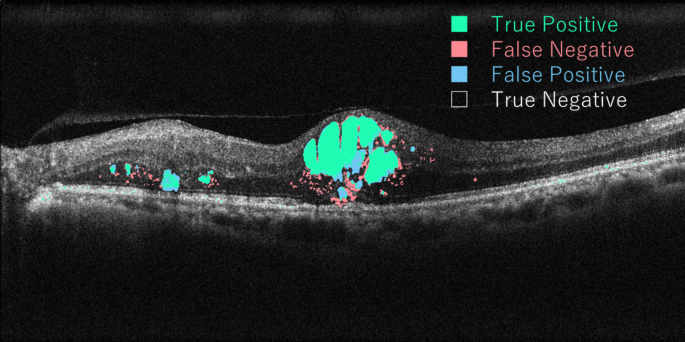

This study has some limitations. First, this study was retrospective, and details of surgical technique, timing and duration of follow-up, and preoperative treatment differed among surgeons, resulting in a selection bias for cystotomy. One of the reasons for the different patients’ treatment backgrounds was that the use of anti-VEGF reagents for DME had not been approved in Japan until 2014. Second, the cystostomy group had fewer eyes than the ILM peeling group because the cystotomy technique is relatively new, so matching the number of cases was difficult. Statistical power analysis to evaluate the reliability of the test results between two groups regarding IMF area showed a beta value of 0.75 in ANOVA, and an increase in the number of cases may lead to significant differences, especially in IMF area. Third, the follow-up period was only one year. To further validate our results on the usefulness of vitrectomy combined with cystotomy, a large prospective controlled study with longer follow-up period is warranted. Finally, the present AI method still has false-positive and false-negative evaluations (Fig. 6), suggesting a potential room for improvement in our model in the future.

The images of the validation data set to evaluate the accuracy of retinal fluid semantic segmentation.

Verification of MF segmentation

In this study, we used a modified deep U-net, which is an improved version of Deep U-Net, a typical neural network used for semantic segmentation. Then, we trained the neural network to generate IMF and OMF probability images from OCT images using our detailed training data. The accuracy of the MF segmentation was evaluated on images from 11 validation datasets (Fig. 6). The accuracy of MF segmentation in the generated segmented images was evaluated by calculating the number of false-positive (FP), false-negative (FN), true-positive (TP), and true-negative (TN) in pixel drawings of MF. Using the parameters, indices to evaluate the accuracy of the deep learning system, such as sensitivity, specificity, overall accuracy, Dice coefficient, and area under the receiver operating characteristic curve (AUC), also were calculated from the equations below: Sensitivity = TP / (TP + FN), Specificity = TN / (TN + FP), Overall accuracy = (TP + TN) / (TP + FP + TN + FN), and Dice coefficient = (2 × TP) / (2 × TP + FP + FN). The AUC was calculated from sensitivity and specificity using scikit-learn module 0.19.1. using Python version 3.6.4. The validation data used in this method was evaluated to have a sensitivity of 0.767, specificity 0.996, accuracy 0.993, AUC 0.986, and Dice coefficient 0.702. This modified deep U-net, which generates predictive images of IMF and OMF by semantic segmentation from DME OCT images, is named “Hokkaido University macular fluid segmentation model”.